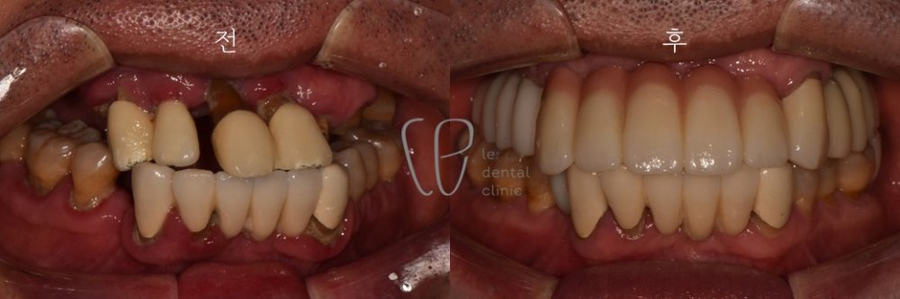

Dental Treatments in Seoul, South Korea Before and After Photos

Le Dental Clinic maintains a gallery showcasing before-and-after photos of various Dental Treatment in Seoul, South Korea, including esthetic treatments, orthodontics, and implant surgeries. These images highlight the clinic's success in transforming smiles and improving dental health.

Before and After Dental Treatment in Seoul, South Korea